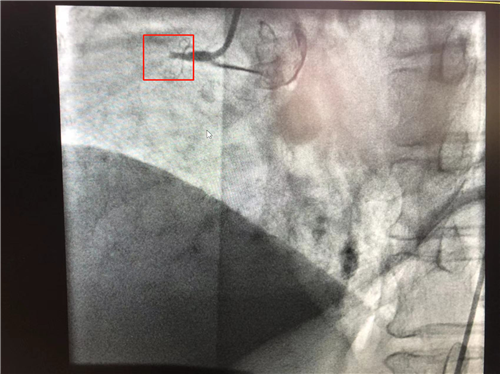

時間就是心肌,時間就是生命。導(dǎo)管室內(nèi),心血管內(nèi)科副主任徐先進、主任助理農(nóng)彥林已然待命,病人一到,團隊立即為其行深靜脈穿刺泵入血管活性藥物等,情況緩解后,行多體位冠狀動脈造影,確認RCA(右冠狀動脈)近端完全閉塞。經(jīng)家屬同意,在汪念東院長的指導(dǎo)下,徐先進、農(nóng)彥林、張星為患者行經(jīng)皮冠狀動脈球囊擴張成形術(shù)+經(jīng)外周靜脈穿刺中心靜脈置管術(shù)。術(shù)中,張奶奶再次出現(xiàn)室顫,心血管內(nèi)科團隊臨危不亂,立即予以300焦電除顫搶救,患者竇性心律恢復(fù)。隨后,球囊擴張為其置入心臟支架,復(fù)查造影顯示血管恢復(fù)暢通,無明顯夾層,殘余狹窄不到10%。術(shù)后,張奶奶血壓偏低,轉(zhuǎn)入ICU無創(chuàng)呼吸監(jiān)護,2天后轉(zhuǎn)回心血管內(nèi)科護理。

術(shù)前:右冠近端閉塞